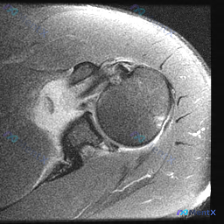

单张肩关节轴位MRI显示盂唇无异常,但临床怀疑盂唇病变,下一步怎么评估?

看到一个肩关节病例,临床怀疑盂唇病变,但只提供了一张轴位T2加权MRI图像。先看影像分析结果:

轴位MRI表现:

- 前、后盂唇形态基本完整,信号均匀,未见明确撕裂信号

- 肩胛下肌腱、冈下肌腱、肱二头肌长头腱信号正常,未见撕裂

- 肱骨头与关节盂对位良好,骨质及软组织未见明显异常

核心矛盾:临床怀疑盂唇病变,但单张影像未显示明确异常。